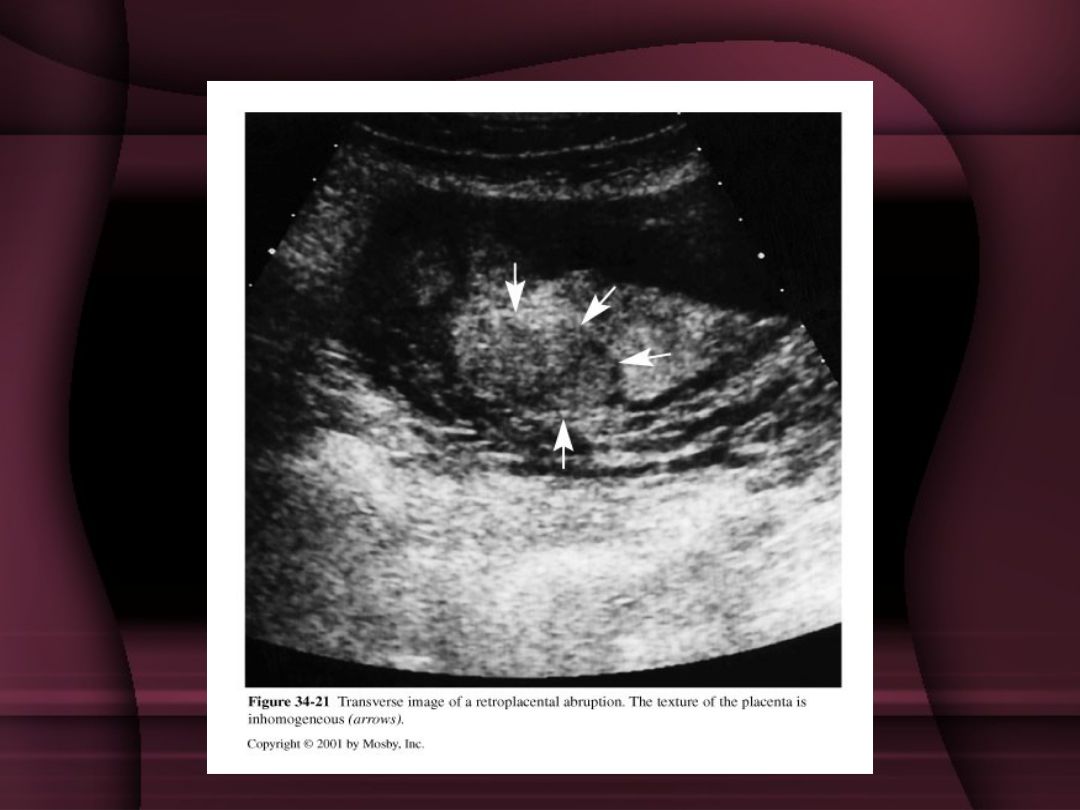

6-8. A 28-year-old G4P2 at 20 weeks' gestation presents for her fetal anatomical survey. There have been no pregnancy complications to date. The placenta is imaged with the findings shown below. What do you document on the ultrasound report?

Posterior placenta

Posterior placenta with chorioangioma

Posterior placenta with succenturiate lobe

Posterior placenta with remote subchorionic hematoma